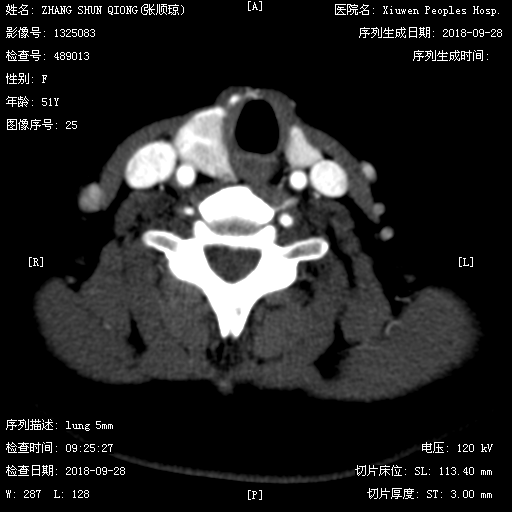

超声 CT平扫

CT平扫 CT增强

CT表现:甲状腺右侧椭圆形低密度影,平扫低密度,增强动脉期轻度磨玻璃样强化,静脉期强化程度低于周围甲状腺实质,病灶范围较平扫缩小,边界变模糊。结合超声,定性恶性,倾向甲状腺髓样癌。

CT四大主征:1.低强化、2.钙化、3.形态规则、4.甲状腺中上极。